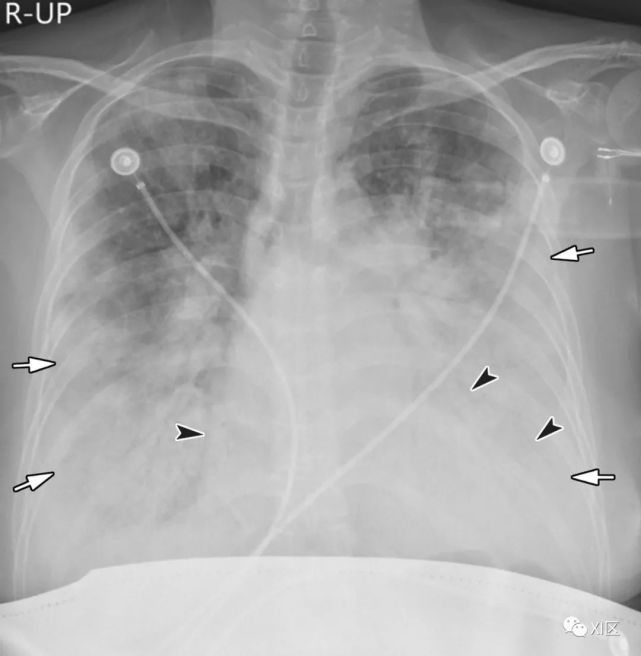

图23 27岁男性,出现咳嗽和咳痰,诊断为MERS冠状病毒引起的肺炎。(上)最初的胸片显示,在下肺的两个区域,特别是在左心后区域,结节影(箭)区域增加。同一天在右下肺静脉水平(中上)以及右心房和下腔静脉交界处(中下)的冠状位重建图像(3mm) 椎体水平的图像(下)显示了两下肺叶的多发斑块状和结节样实变和GGO(箭头)。

Koo H J , Lim S , Choe J ,et al. Radiographic and CT Features of Viral Pneumonia[J]. Radiographics, 2018, 38(3):719-739.